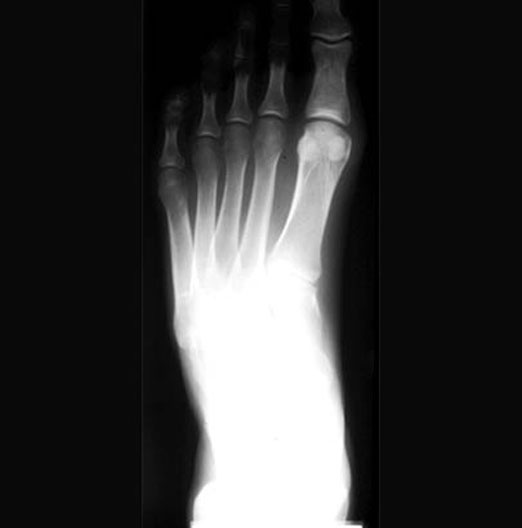

Foot Dorsoplantar Projection

1. Proximal phalanx

2. Sesamoid bones

3. 1st metatarsal bone